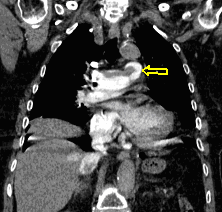

2b. Atelectasis, left upper lobe. CECT, coronal reconstr. (by the contribution of Zsuzsanna Monostori, MD, PhD)

6. c

Image

6. d

64 year old man. Infiltration and abscess development in the right lower lobe.

c.) CT lung window, coronal reformat, d.) axial, mediastinal window. Extensive area in the right 8-9th segments without air, including many associated lesions of fluid density, with tiny air bubbles, larger air spaces and air-fluid level. The lesion has almost a triangular shape, its dorsal and ventral contours are arched, its peak points towards the lower pole of the hilum.